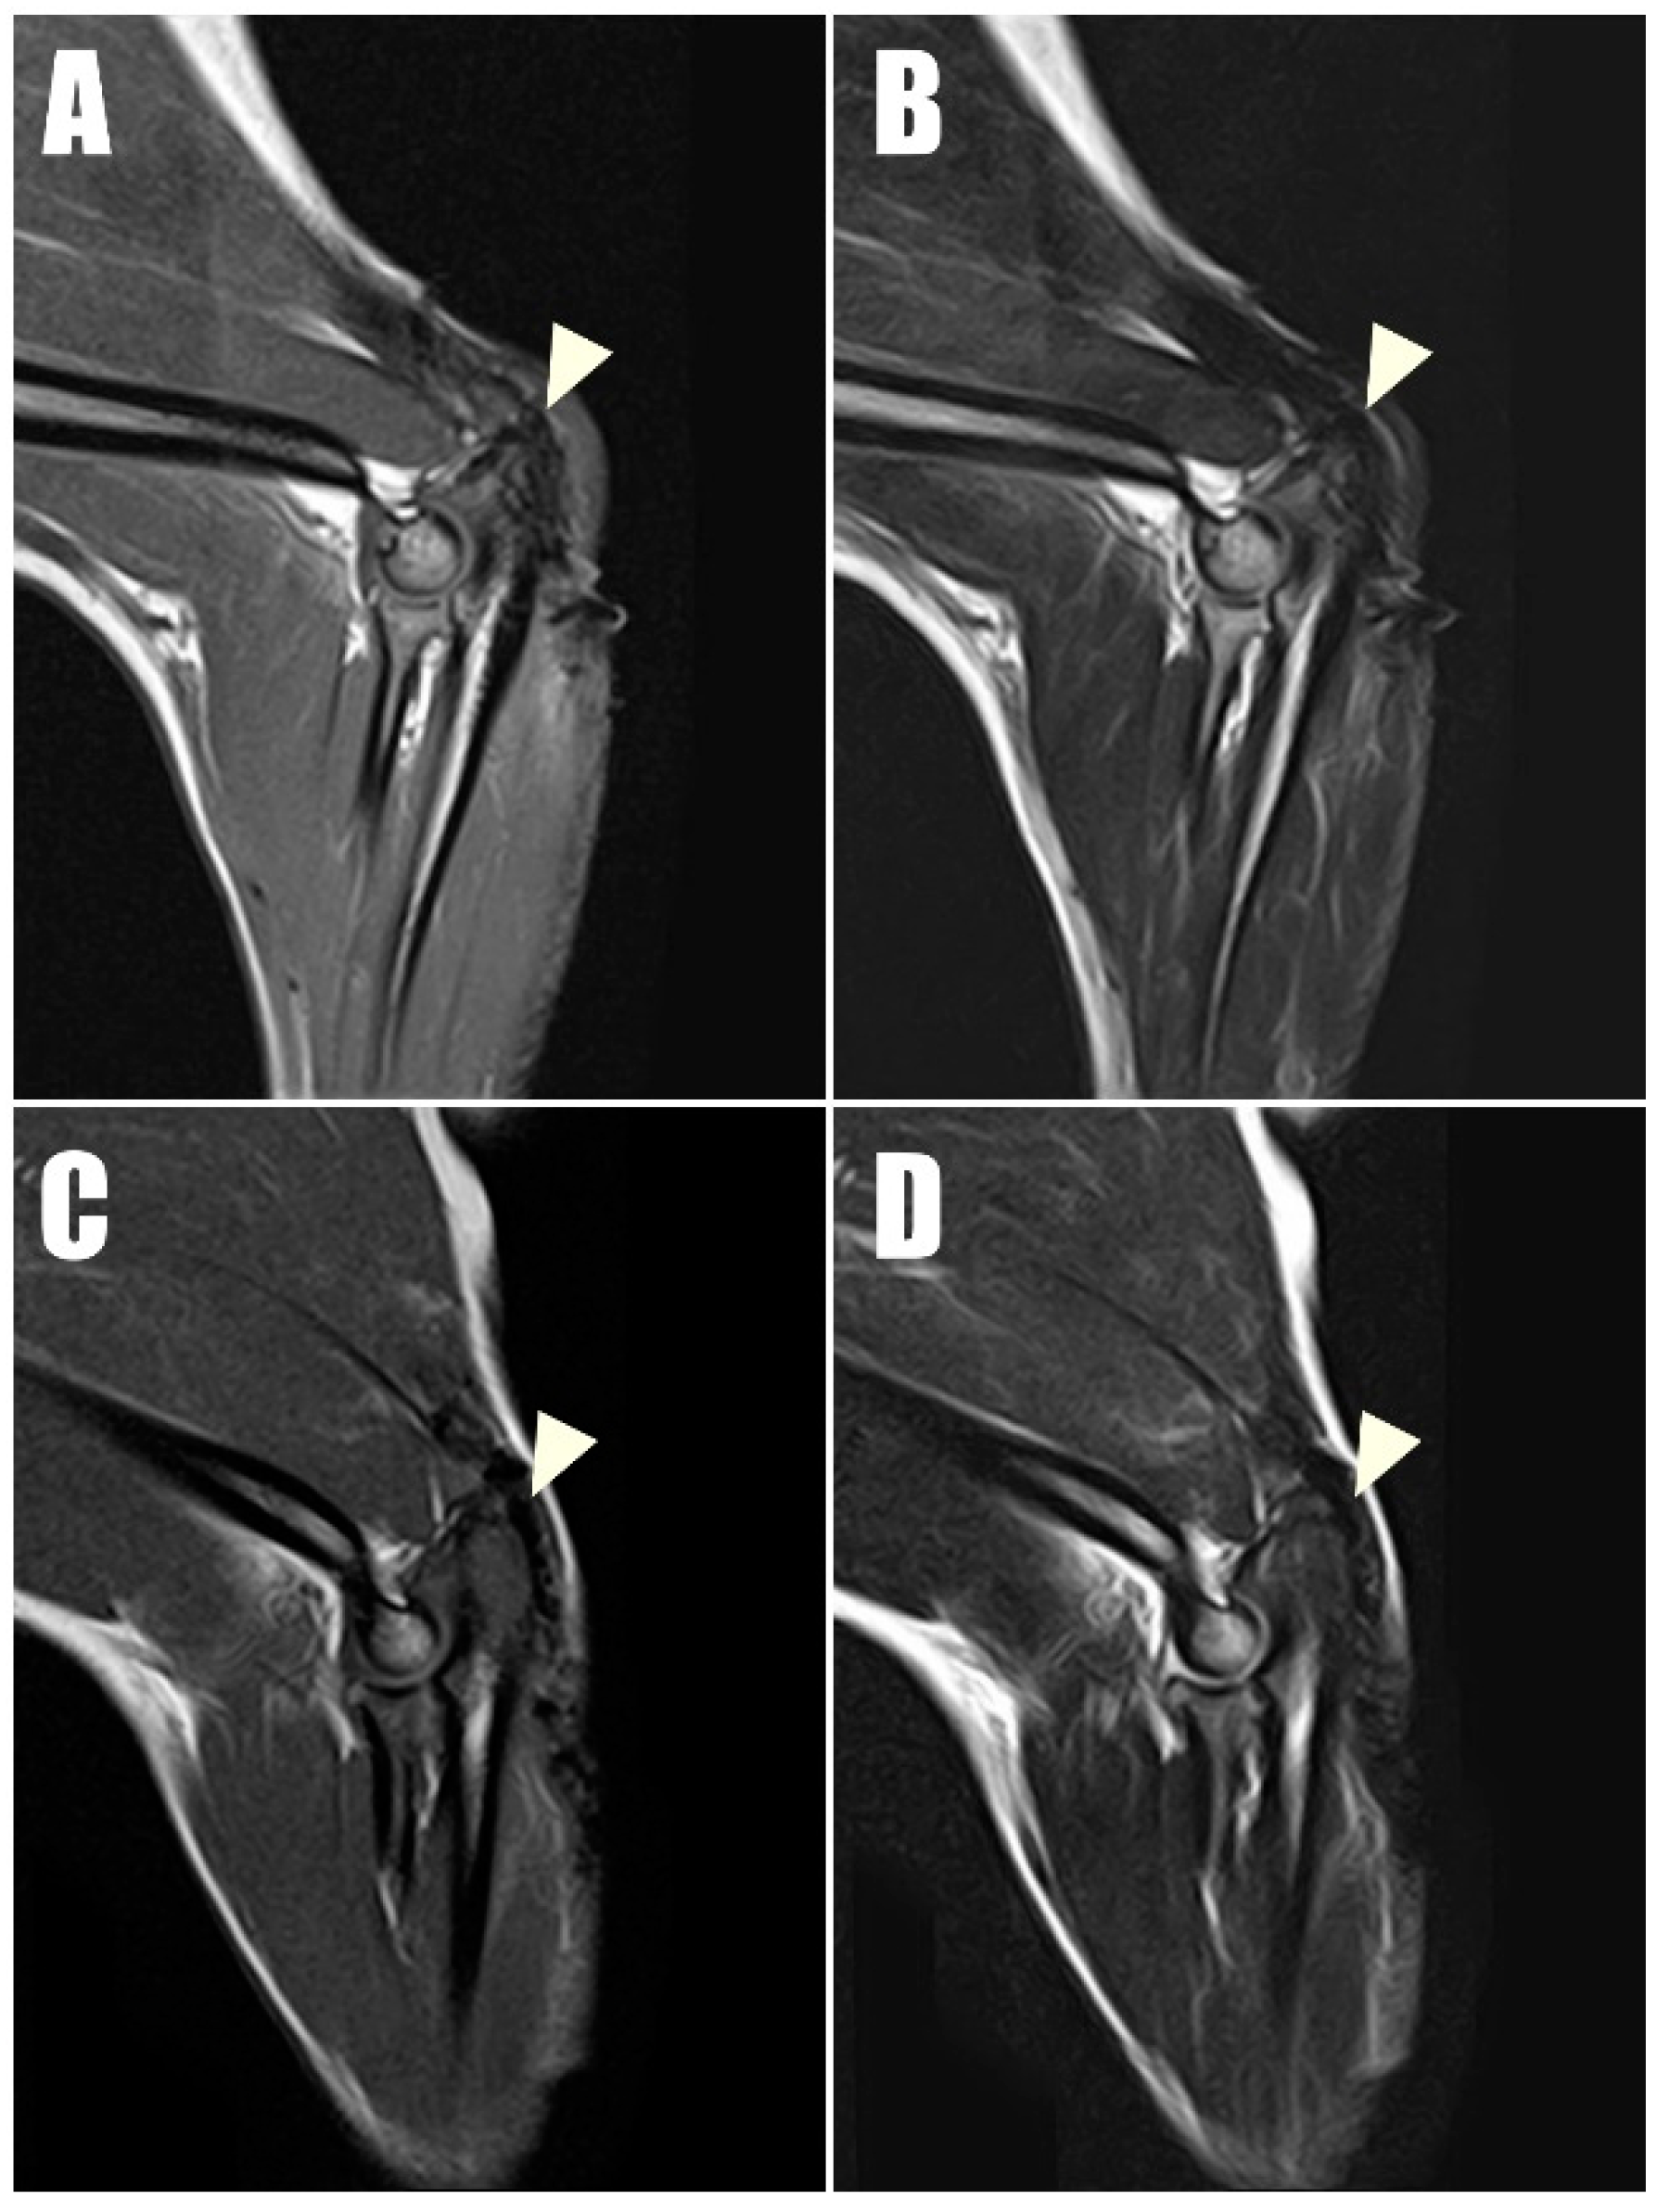

Radiography (Figure 6C,D) and ultrasonography (Figure 7C,D) six months postoperatively confirmed that the transverse hole of the right side healed without any complications, and the bilateral triceps brachii tendons were well-maintained and attached to the olecranon, with no specific changes in internal echogenicity or echotexture. MRI (Figure 8) showed mild inflammatory changes near the suture knot and fibrotic scar tissue within the tendon but confirmed firm attachment of the tendon to the olecranon. Three years following the surgery, the patient exhibited no signs of functional loss (Video S2) or pain, confirming the long-term success of the treatment. The owner expressed satisfaction with the clinical outcomes.

Tendon structural integrity and musculotendinous change are best evaluated by magnetic resonance imaging (MRI). In the late stages of tendon healing, tendons typically exhibit low signal intensity across T1- and T2-weighted MRI sequences [23]. In the current case, the bilateral triceps brachii tendons at their attachment to the olecranon demonstrated low signal intensity in all sequences at the one-year postoperative evaluation, with the exception of mild inflammatory changes observed near the suture knots and surrounding scar tissues.

Figure 8. Postoperative magnetic resonance imaging (MRI) taken one year postoperatively captured (A) T1-weighted and (B) T2-weighted sagittal images of the right triceps brachii tendon, along with (C) T1- T1-weighted and (D) T2-weighted sagittal images of the left of triceps brachii tendon. These images demonstrate low signal intensity on both T1 and T2 sequences, indicating intact connectivity of the tendon.